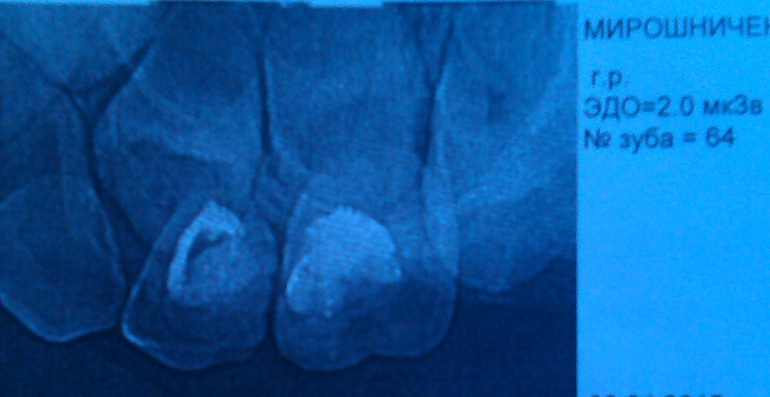

Здравствуйте! В 4-4,5 года дочери лечили пульпит верхней 4ки. В 5 лет она жаловалась на незначительную боль в области этого зуба, сделали снимок, сказали, что всё в порядке и лучше вычищать межзубное пространство, что болит воспаленная десна между 4 и 5. Больше боль не беспокоила и вот почти в 6 лет зуб резко заболел. Вокруг воспаленная десна и немного подвижен. Удалили. Это снимок в 5 лет

На таком рентгеновском снимке не понять- есть ли воспаление, т.к. уж сильно много наложений. В таких случаях мы переделываем снимок, но имеем, что имеем.

А вот про вопрос перфорации- можно ли мне снимок зуба ближе? Чтобы четче было видно отверстие.